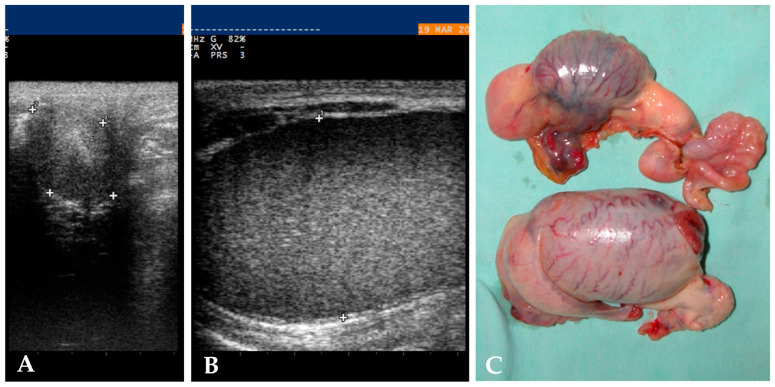

多年来,各种诊断和外科技术已经发展到识别和治疗马科隐睾。本研究回顾性分析了2012年至2025年间两个中心的隐睾病例。收集的临床资料包括品种、品种、年龄、性别、保留睾丸的位置、诊断方法、麻醉方案和手术治疗、围手术期药物治疗、术中并发症和结局。共纳入37例临床病例,1/37为驴,1/37为双性母。大多数马都是三岁的,属于西部骑马品种。超声检查在87%的病例中正确地确定了保留睾丸的位置。麻醉方案包括局部麻醉阻滞,主要是局部注射以浸润保留的睾丸。腹腔镜站立侧腹技术是主要的入路,占82%的病例。并发症发生率为9%,中位出院时间为2天。在我们的研究中,四分之一马类型的马被过度代表,并且有三匹马是同一种马的儿子,这表明病因有遗传成分。超声检查可在腹部和腹股沟部位确认隐睾。站立式侧腹腹腔镜是最常选择的手术,超过了卧位腹腔镜和腹股沟开放式睾丸切除术。结果报告术中并发症发生率低。

Over the years, various diagnostic and surgical techniques have been developed to recognise and treat cryptorchidism in equid. This study retrospectively analysed cases of cryptorchidism referred to two centres between 2012 and 2025. Clinical data collected included species, breed, age, gender, location of retained testis, diagnostic approach, anaesthesia plan and surgical treatment, perioperative medical treatment, intra-operative complications and outcomes. A total of 37 clinical cases were included, 1/37 was a donkey and 1/37 was an intersex female. Most of the horses were three years old and belonged to western riding horse breeds. Ultrasound examination correctly identified the location of the retained testis in 87% of cases. The anaesthesia plan includes a local anaesthesia block, mainly a local injection for the infiltration of the retained testis. The laparoscopic standing flank technique was the main approach, performed in 82% of cases. Complications were encountered in 9% of cases, and the median discharge time was 2 days. In our study, Quarter Horse-type horses were overrepresented, and three horses were sons of the same Quarter Horse stallion, suggesting a genetic component in aetiology. The use of ultrasound might confirm cryptorchidism in both abdominal and inguinal locations. Standing flank laparoscopy was the most frequently chosen procedure, over recumbent laparoscopy and inguinal open orchiectomy. The outcome reported a low rate of intra-operative complications.